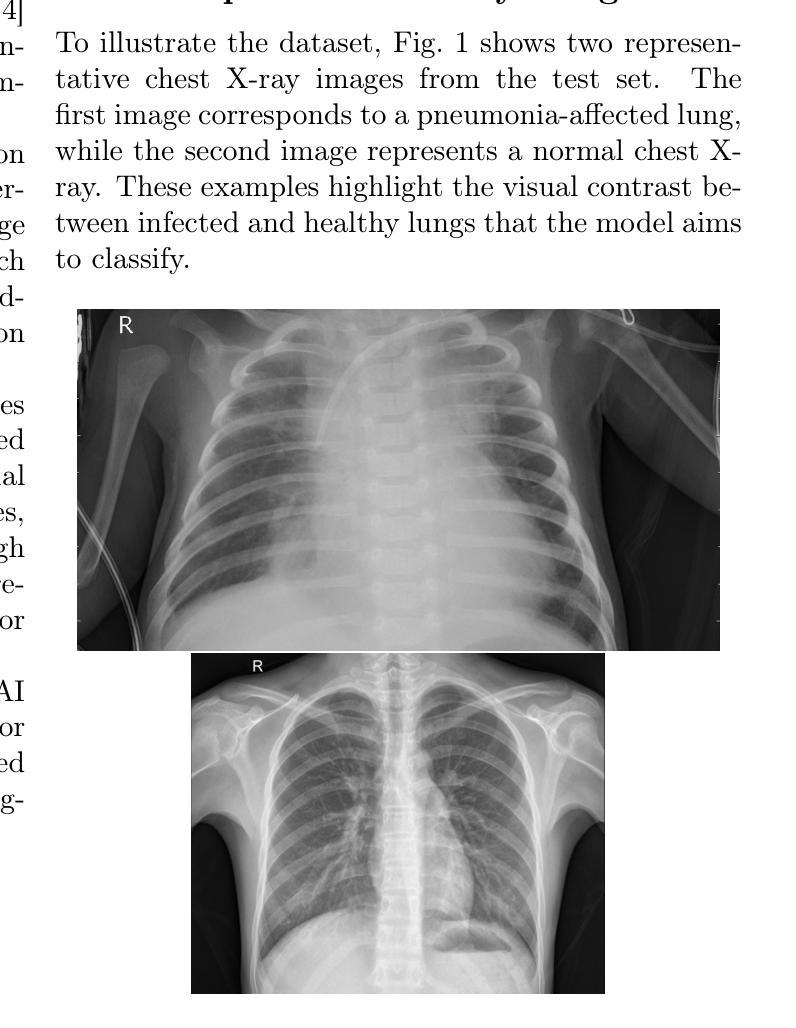

In this study, we evaluate the ability of OpenAI’s gpt-4o model to classify chest X-ray images as either NORMAL or PNEUMONIA in a zero-shot setting, without any prior fine-tuning. A balanced test set of 400 images (200 from each class) was used to assess performance across four distinct prompt designs, ranging from minimal instructions to detailed, reasoning-based prompts. The results indicate that concise, feature-focused prompts achieved the highest classification accuracy of 74%, whereas reasoning-oriented prompts resulted in lower performance. These findings highlight that while ChatGPT exhibits emerging potential for medical image interpretation, its diagnostic reliability remains limited. Continued advances in visual reasoning and domain-specific adaptation are required before such models can be safely applied in clinical practice.

本研究评估了OpenAI的gpt-4o模型在零样本设置下对胸部X射线图像进行分类的能力,将其分为正常或肺炎两类,且无需进行任何先前的微调。使用包含400张图像(各200张)的平衡测试集来评估四种不同提示设计的性能,提示设计范围从简单的指令到详细、基于推理的提示。结果表明,简洁、以特征为中心的提示获得了最高的分类准确率(即74%),而基于推理的提示则导致性能下降。这些发现表明,虽然ChatGPT在医学图像解释方面显示出新兴潜力,但其诊断可靠性仍然有限。在将这种模型安全应用于临床实践之前,还需要在视觉推理和特定领域的适应性方面进行持续进步。

Summary:本研究评估了OpenAI的gpt-4o模型在零样本设置下分类胸部X光图像的能力,无需任何先前的微调。使用包含400张图像(每个类别各200张)的平衡测试集来评估四种不同提示设计的性能,从简单的指令到详细的基于推理的提示。结果表明,简洁、以特征为中心的提示获得了最高的分类准确率(74%),而基于推理的提示则表现较差。这些发现表明,虽然ChatGPT在医学图像解读方面显示出新兴潜力,但其诊断可靠性仍然有限。需要进一步提高视觉推理和领域特定适应性才能将这些模型安全应用于临床实践。